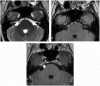

Intracranial trigeminal schwannomas are rare tumors. Patients usually present with symptoms of trigeminal nerve dysfunction, the most common symptom being facial pain. MRI is the imaging modality of choice and is usually diagnostic in the appropriate clinical setting. The thin T2-weighted CISS 3D axial sequence is important for proper assessment of the cisternal segment of the nerve. They are usually hypointense on T1, hyperintense on T2 with avid enhancement post gadolinium. CT scan is supplementary to MRI, particularly for tumors located in the skull base. Imaging plays a role in diagnosis and surgical planning. In this pictorial essay, we retrospectively reviewed imaging findings in nine patients with pathologically proven trigeminal schwannoma. Familiarity with the imaging findings of intracranial trigeminal schwannoma may help to diagnose this entity.